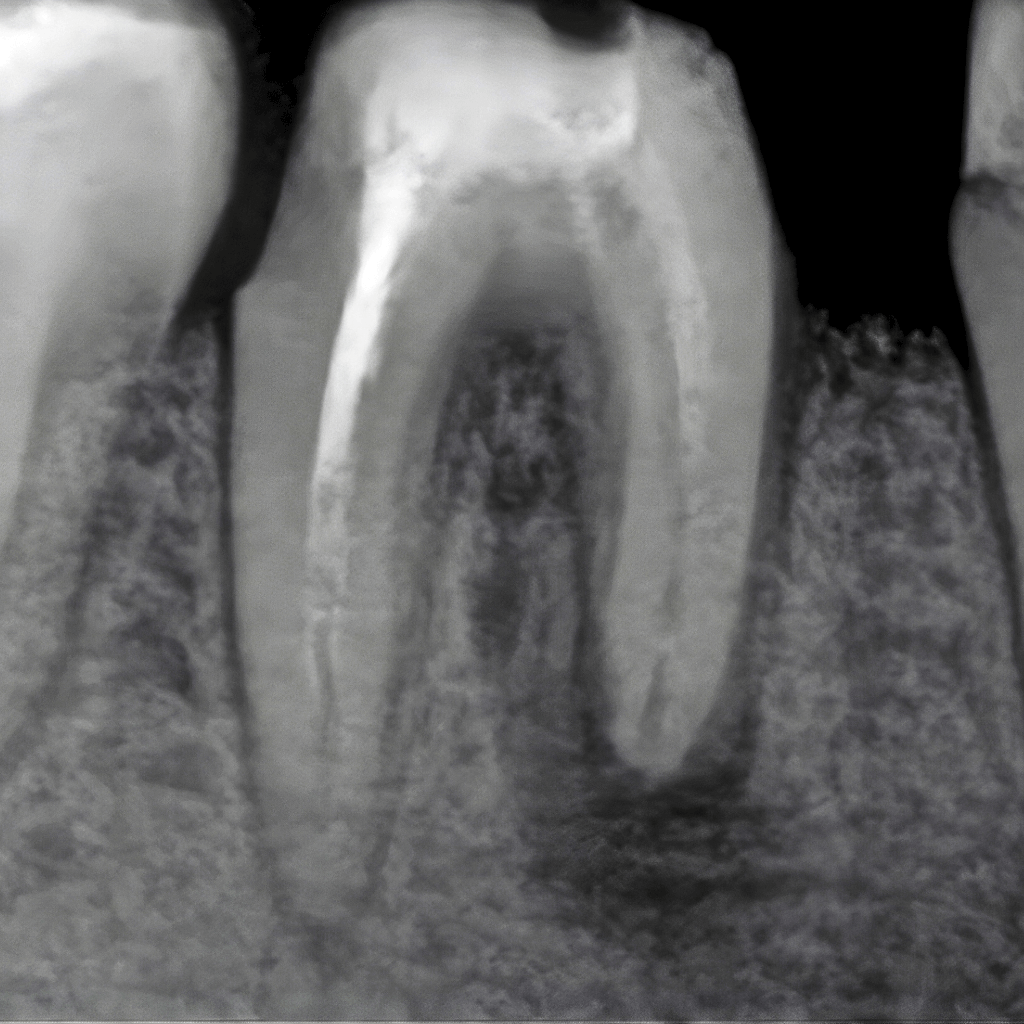

Оценяваме състоянието на зъба и кореновата система чрез клиничен преглед и образна диагностика, за да планираме лечението прецизно.

Инфектираните тъкани се отстраняват внимателно, а каналите се обработват механично и ръчно, с цел пълно почистване.

Каналите се дезинфекцират и оформят така, че да бъдат подготвени за надеждно запълване.

Кореновите канали се запълват херметично с биосъвместим материал, който предотвратява повторна инфекция.